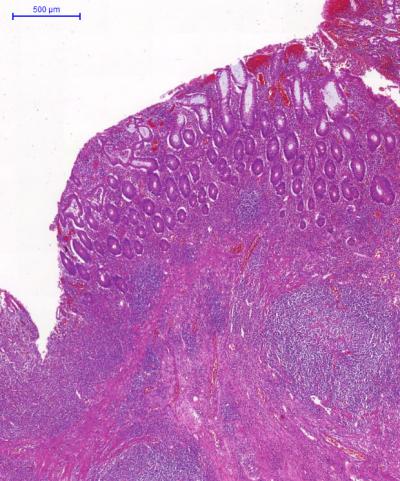

T cells are important in fighting infection as they're mostly designed to act against foreign invaders to the body such as pathogens. But there are some T-cells that react and attack our own tissues, resulting in autoimmune diseases, such as type I diabetes and rheumatoid arthritis. Regulatory T cells are crucial cells in stopping these harmful T cells from causing disease, and are therefore being used as potential therapies to treat autoimmune diseases.

The Manchester researchers have identified new and crucial molecules which allow regulatory T cells to function and cure active inflammation during disease.

Dr Travis explains the importance of their work: "Regulatory T cells are already being used in clinical trials where the cells are taken from the patient, multiplied and then given back to the patient to suppress their illness. By understanding the mechanisms behind how regulatory T cells work, we could improve on these therapies, which can be potentially useful in conditions ranging from type 1 diabetes to multiple sclerosis, rheumatoid arthritis and inflammatory bowel disease.